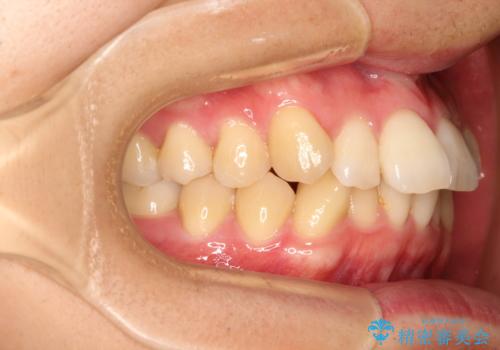

前歯の凸凹をきれいにしたい。インビザラインによる治療

- 前歯の凸凹を主訴に来院された患者様です。

インビザラインにて治療を行いました。